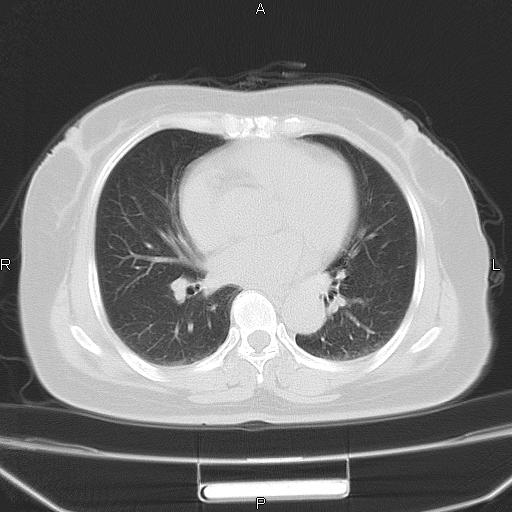

胸腺瘤

女、63Y 双眼睑下垂,早轻晚重。 胸腺瘤???

结果胸腺瘤